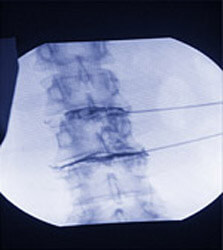

Bei Bandscheibenvorfällen führen wir zum gegenwärtigen Zeitpunkt primär die intradiskale elektrothermische Bandscheibenverschmelzung (Dekompression) durch. Hierbei gelangt man unter Umgehung des Rückenmarkskanals von außen in das Bandscheibenfach und appliziert einen kleinen Katheter, der anschließend über 12 bis 16 Minuten auf eine Temperatur von 90° C erwärmt wird. Hierbei kommt es durch einen Verschmelzungsvorgang und demzufolge zu einem Schrumpfen der vorgefallenen Bandscheibenanteile (siehe www.neurotherm.com unter Dekompression). Dieses Verfahren wird von einer Radiofrequenz-Technik in Form der Nukleoplastie (www.nucleoplasty.com) unter gleicher Vorgehensweise ergänzt.

Seit Herbst 2006 führen wir als erste Praxis bei größeren Bandscheibenvorwölbungen ebenfalls ein perkutanes (nur durch die Haut ohne öffnung mittels Schnitt) Verfahren durch, das sich durch die Applikation eines Wassermessers auszeichnet. Mit diesem Wassermesser, welches ebenfalls sehr klein ist, wird durch einen Druck von nahezu 1.000 bar sehr schonend das Bandscheibengewebe reduziert. All diese Verfahren werden unter Lokalnarkose durchgeführt und sind in der Regel nahezu schmerzfrei.

Bilder zu Minimal-invasive Schmerztherapie